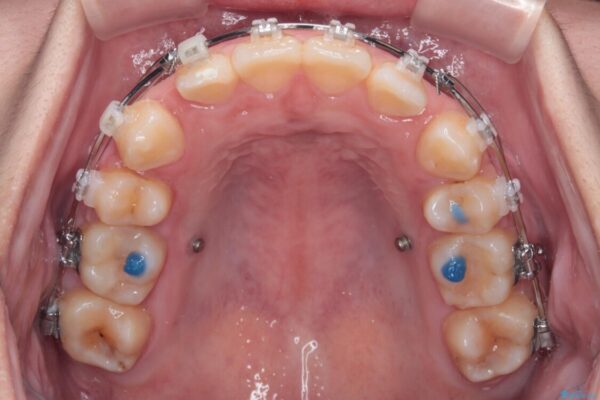

治療途中

• 転勤でも安心して治療継続 抜歯スペース閉鎖と深い噛み合わせ改善のワイヤー矯正 治療途中画像